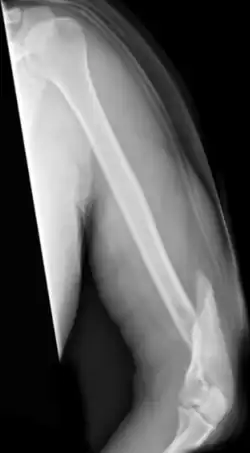

Humerusfraktur

Als Humerusfraktur werden Brüche des Oberarmknochens bezeichnet.

- Humerusschaftfraktur: Brüche des Oberarmschaftes.